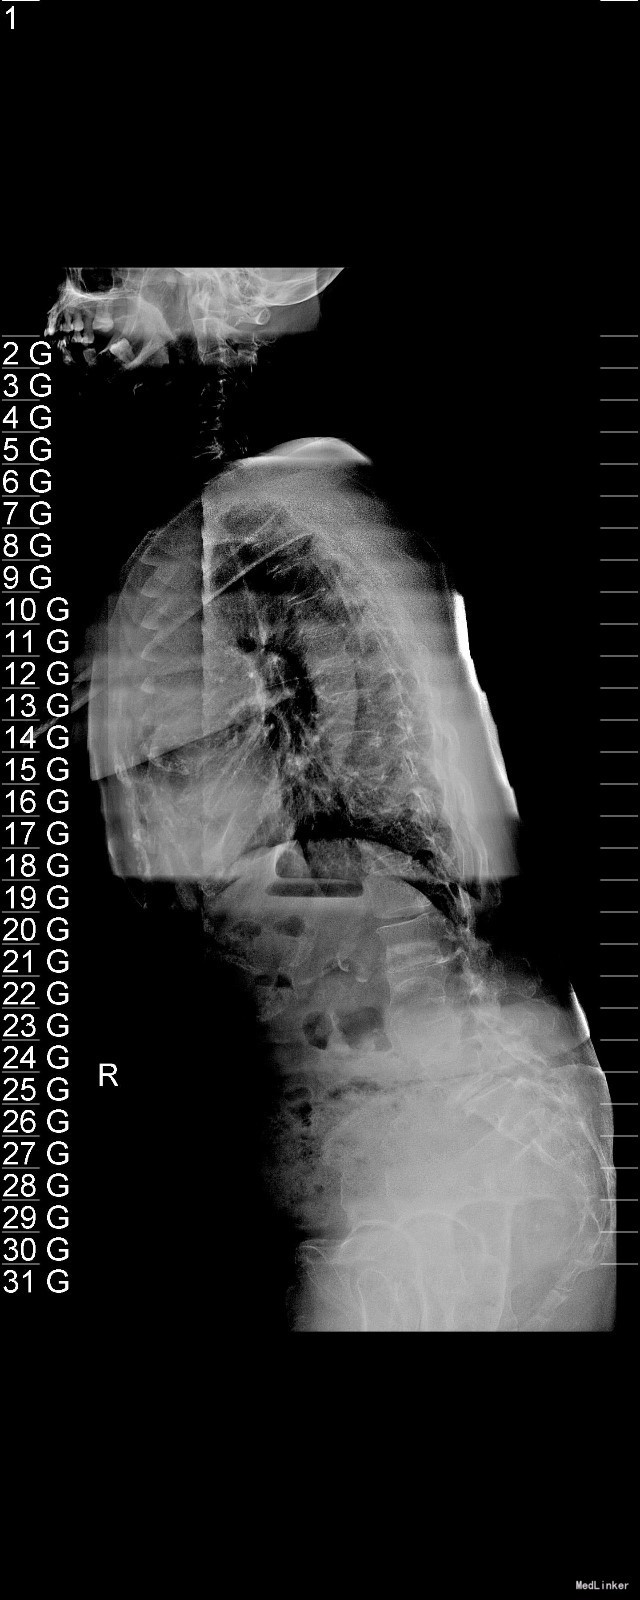

主诉:右下肢麻木11年,腰部酸痛无力 现病史:女性患者,65岁,患者于11年前无明显诱因下出现右下肢麻木,自大腿至右踝部,站立位加重。未予重视,后期出现腰臀部僵硬,弓背僵硬无力,自主行走距离不足200米,曾于06年经X线平片及MRI检查:腰椎椎管狭窄伴有腰椎滑脱,椎间盘突出等。

查体:侧弯畸形,右臀部及右下肢麻木疼痛,腰部活动受限,难以站立。右侧支腿抬高试验60°。双下肢肌力肌张力可。 辅助检查:平片:腰椎侧弯,椎体滑脱,曲度后凸 磁共振:L2-3,L4-5,L5-S1腰椎椎管狭窄,l2-3L3-4L4-5L5-S1腰椎间盘突出,腰椎退变

诊断: 腰椎侧弯,腰椎间盘突出 治疗:1期微创侧路椎体融合术+2期 微创后路经皮内固定术

随访:患者戴支具术后可早期下床活动,术后三周后行后路固定手术